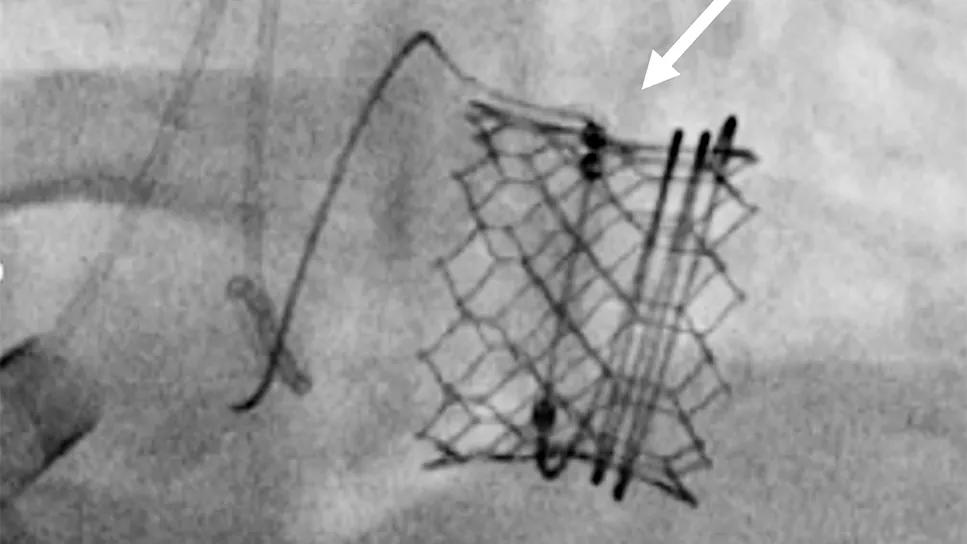

Based in part on the ENCIRCLE findings, the M3 system (Figure 1) was approved by the FDA in December 2025. It is the first transseptal TMVR device approved in the U.S., joining the previously approved Tendyne system, which is delivered transapically.

Figure 1. Placement of the M3 balloon-expandable valve for TMVR. A “dock” is placed in the mitral subvalve (left), after which the balloon-expandable valve is placed inside the dock (middle). An echocardiogram shows the valve in place (right).